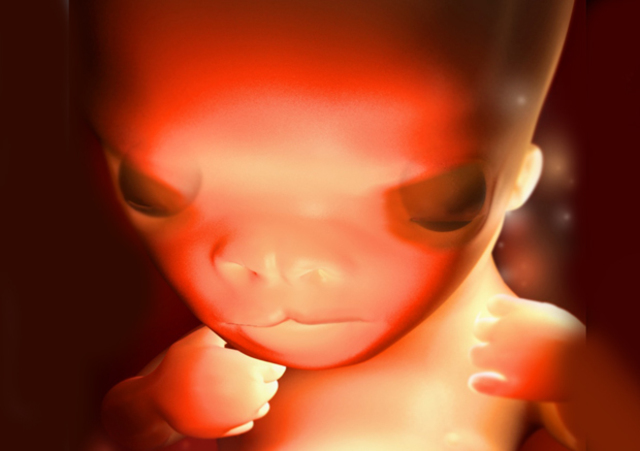

El cerebro crece rápidamente y alcanza el desarrollo completo. En la cara comienzan a apreciarse facciones humanas. Se han formado las cuerdas vocales y el feto es capaz de emitir sonidos. Aparecen las uñas. El feto muestra reflejos, su piel es sensible. Crece alcanzando 76 mm.